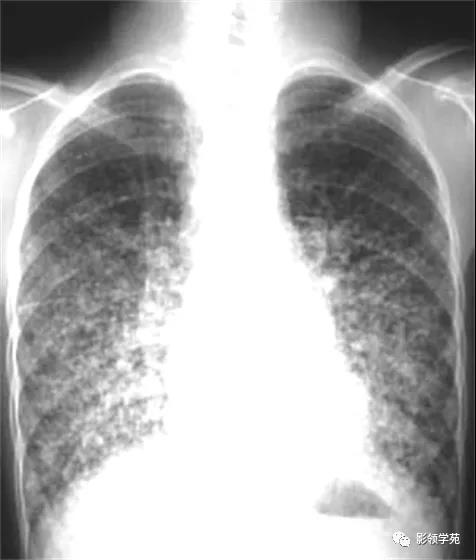

双肺淋巴道转移癌。胸部正位片示双侧中下肺野多发结节状及网格状高密度结节影,可见克氏B线(下图)

淋巴转移:肺门影增大,自肺门向外部规则索条状影(下图)